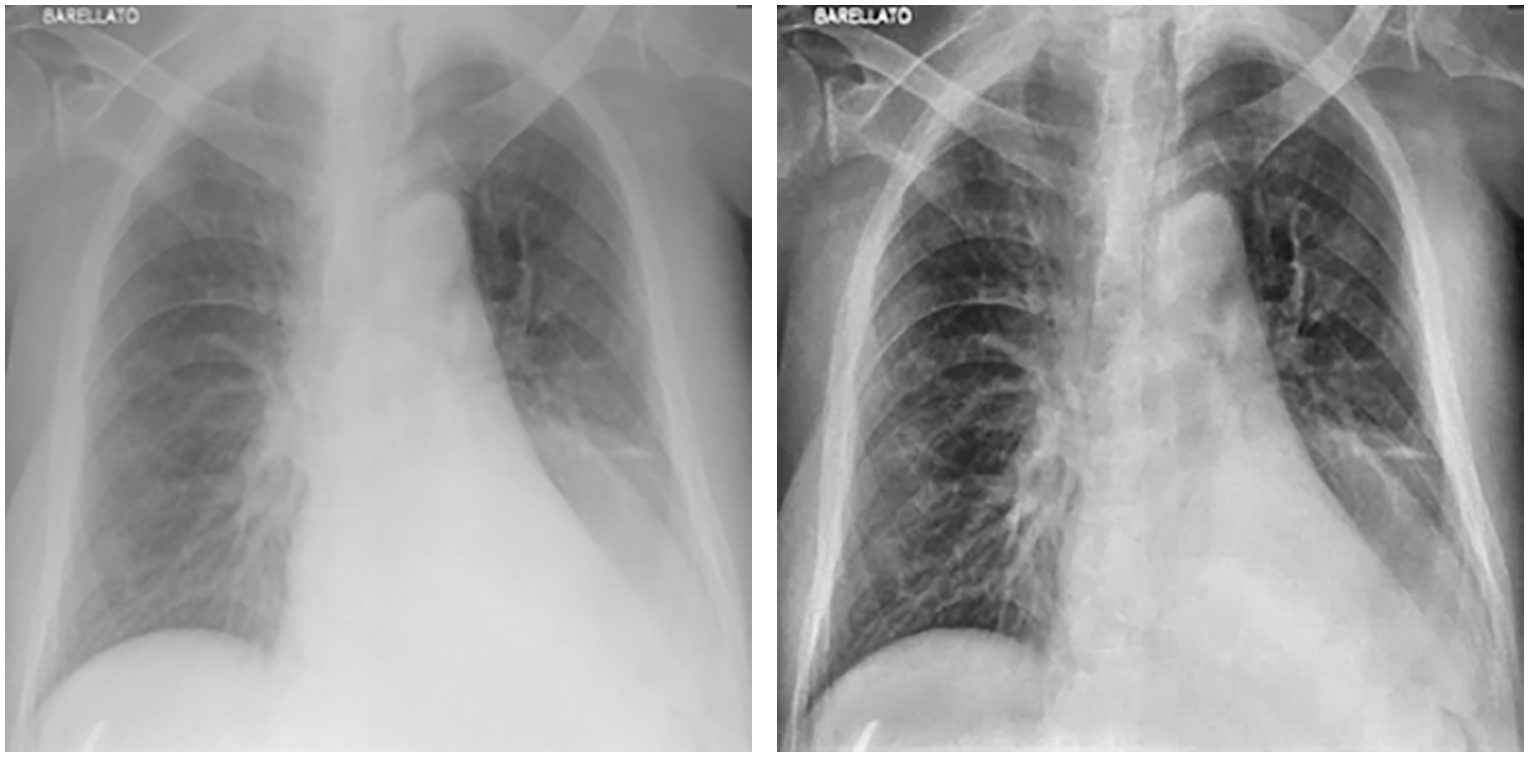

In the first stage, images were cleaned using CLAHE, and augmentation was applied. Fig. 3 shows images before and after applying CLAHE, while Fig. 4 shows images generated via data augmentation.

Figure 3: Chest X-ray before (left) and after (right) applying CLAHE